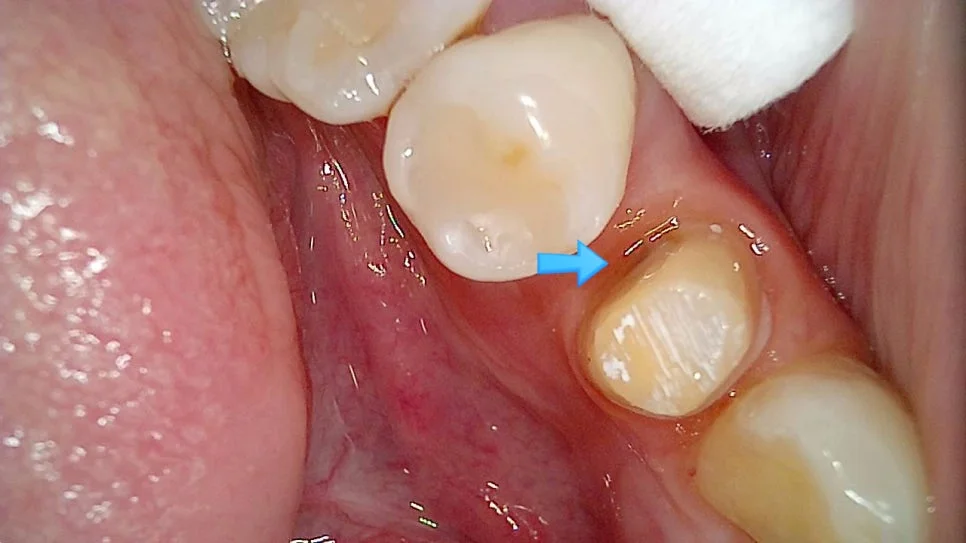

사례 1: 임플란트 보철 재제작으로 음식물 끼임 해결

왼쪽 아래 잇몸의 통증을 호소하신 환자분입니다.

임플란트 음식물 끼임 잇몸 부음 사진

음식물이 고여 있고 주변 잇몸이 부어있는 상태

임플란트와 인접 치아 사이 틈새

임플란트와 바로 앞 치아 사이가 문제

사진을 보면 음식물이 고여 있고 주변 잇몸은 많이 부어있는 양상인데요. 임플란트와 그 바로 앞 치아 사이가 문제입니다.